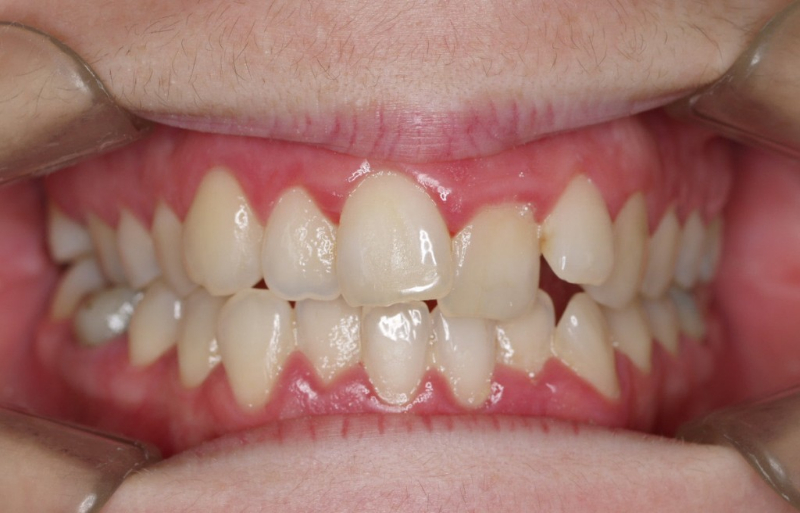

Premolar mandibular incluido + fenestración

45 incluido